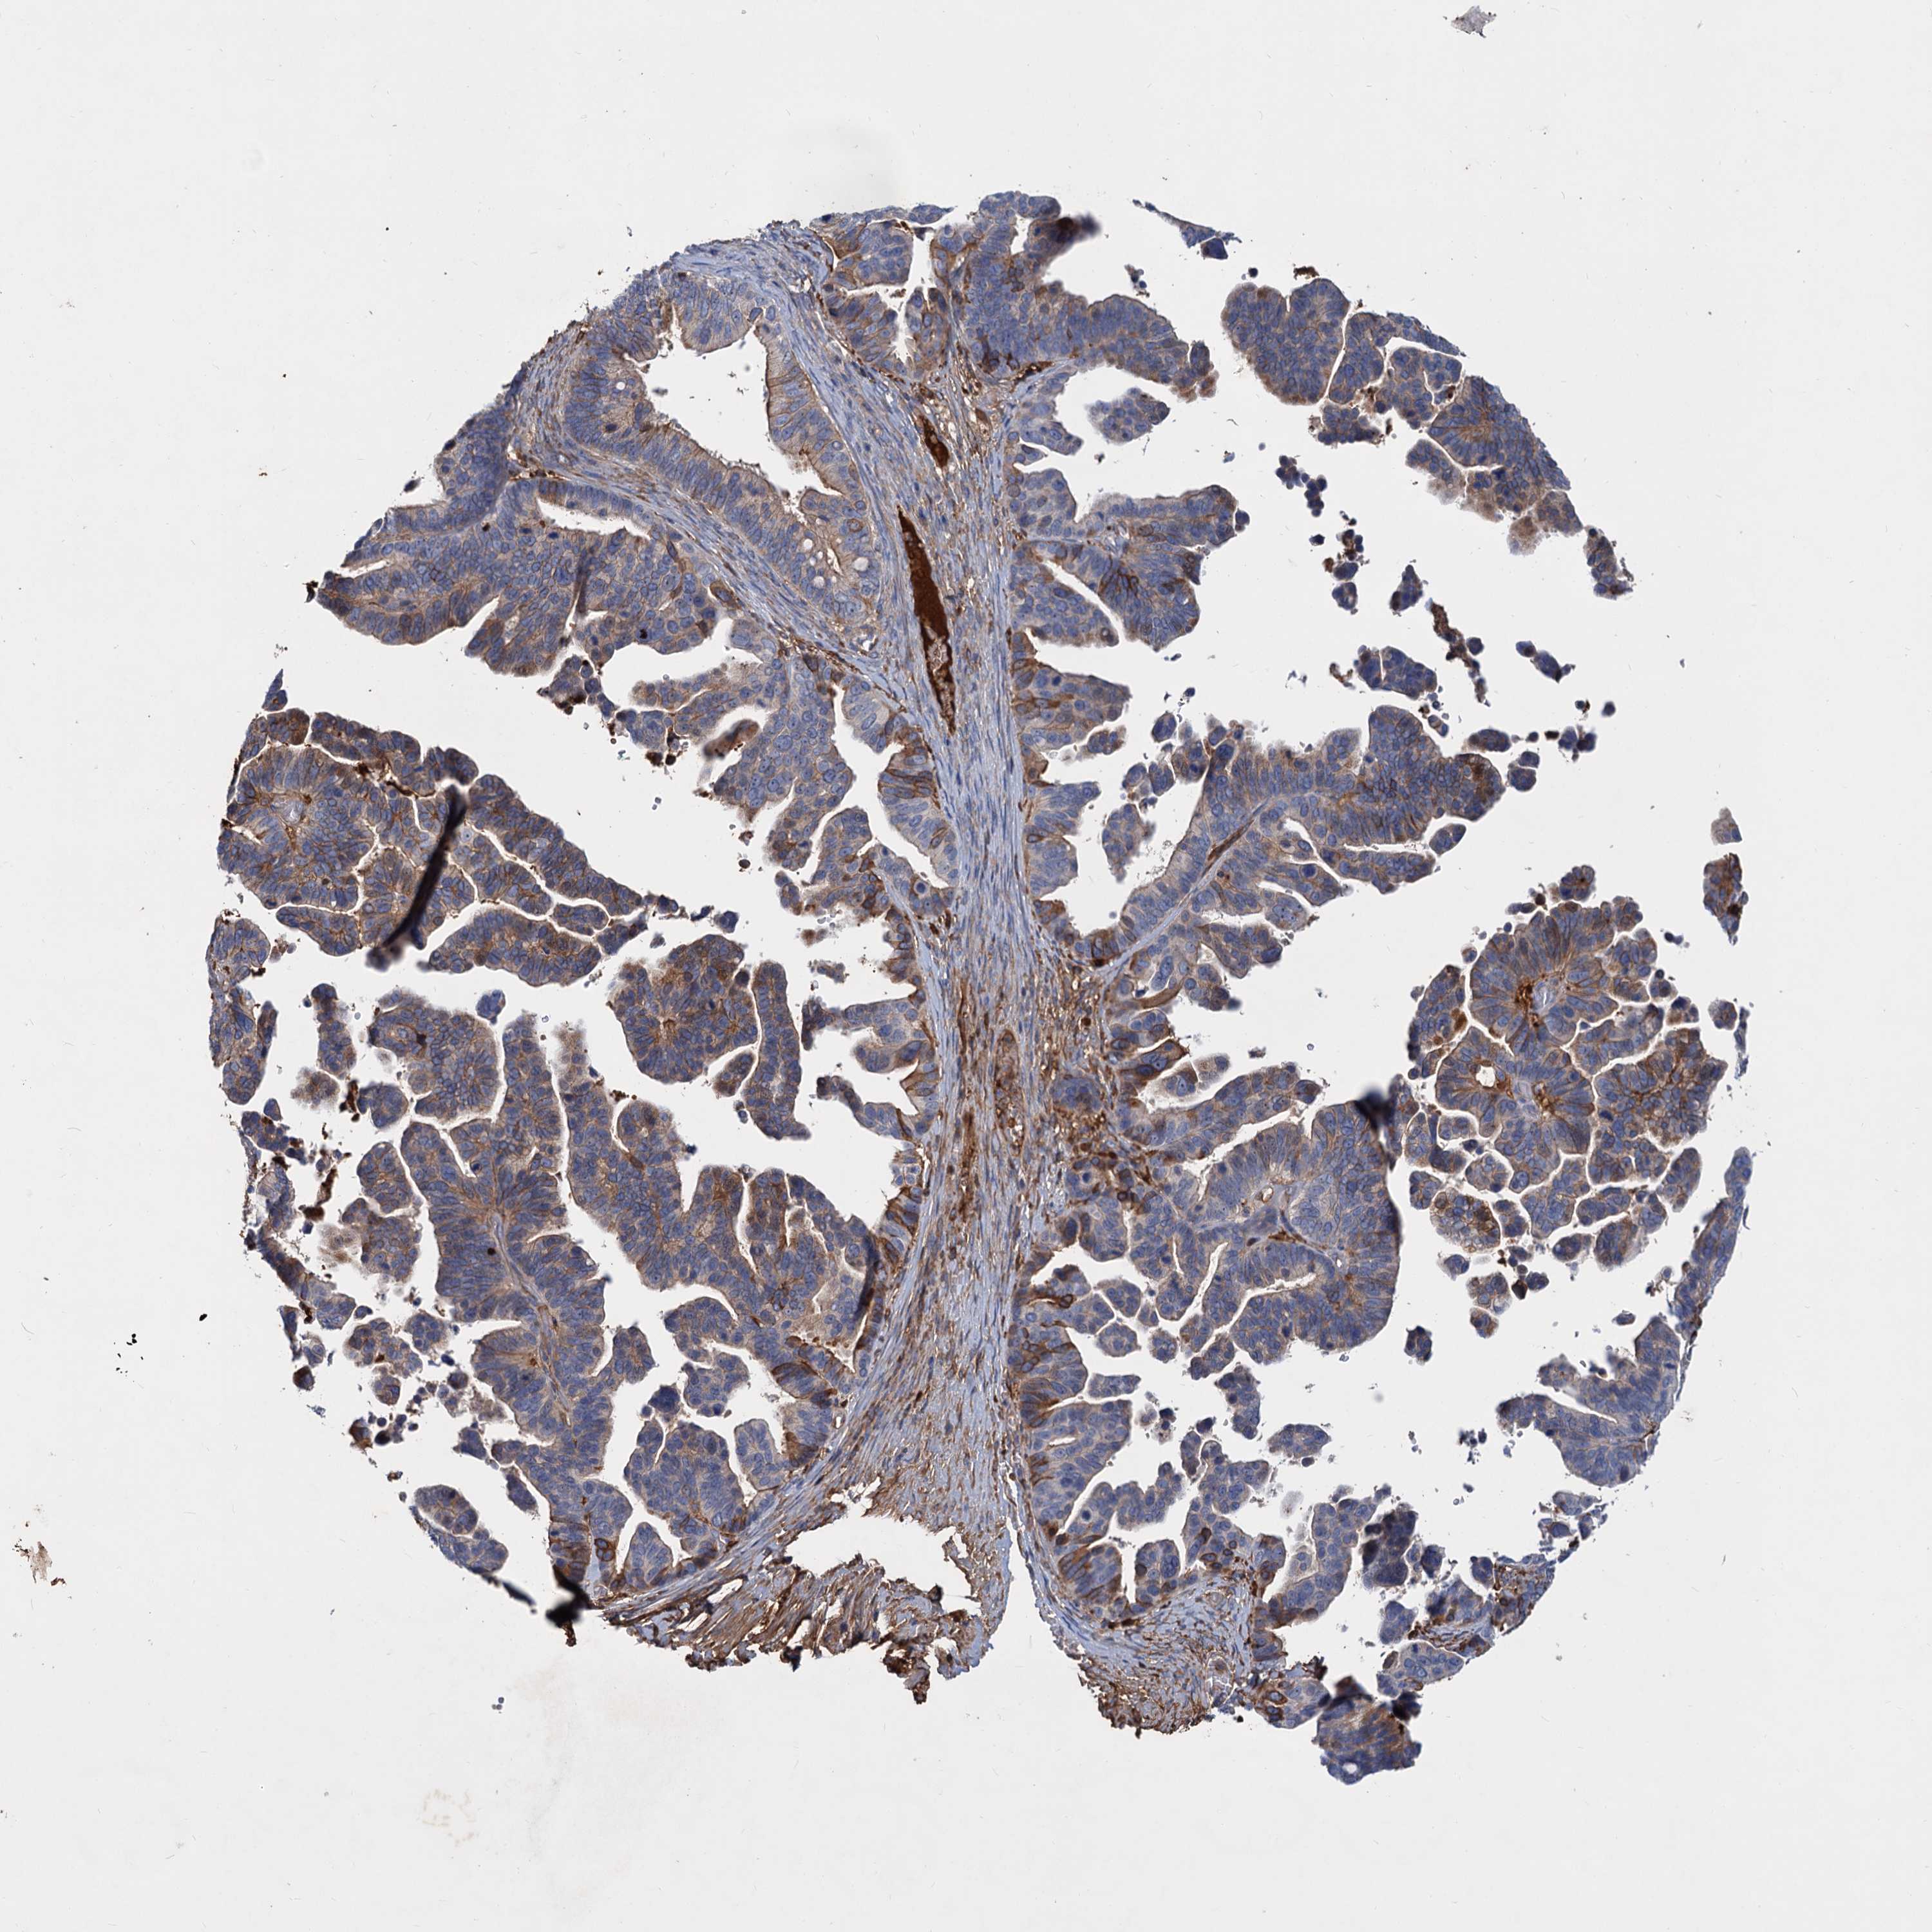

OVARIAN CANCER - Protein expressioni

A mouse-over function shows sample information and annotation data. Click on an image to view it in a full screen mode. Samples can be filtered based on level of antibody staining by selecting one or several of the following categories: high, medium, low and not detected. The assay and annotation is described here.

Note that samples used for immunohistochemistry by the Human Protein Atlas do not correspond to samples in the TCGA dataset.

Antibody stainingi

Antibody staining in the annotated cell types in the current human tissue is reported as not detected, low, medium, or high, based on conventional immunohistochemistry profiling in selected tissues. This score is based on the combination of the staining intensity and fraction of stained cells.

Each image is clickable and will lead to virtual microscopy that enables deeper exploration of all samples and also displays staining intensity scores, fraction scores and subcellular localization as well as patient and tissue information for each sample.

Antibody HPA035827

Staining

High

Medium

Low

Not detected

Intensity

Strong

Moderate

Weak

Negative

Quantity

>75%

75%-25%

<25%

None

Location

Nuclear

Cytoplasmic/membranous

Cytoplasmic/membranous,nuclear

Cystadenocarcinoma, serous, NOS

Carcinoma, endometroid

Cystadenocarcinoma, mucinous, NOS

Carcinoma, NOS